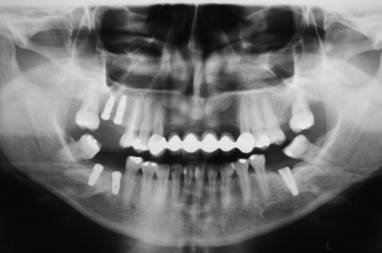

Figura 4. Radiografia panorâmica dos implantes antes do início da etapa protética – baseline.  Este exame é ideal para observar o posicionamento da plataforma do implante com relação à crista óssea distal e mesial. Observar ainda o correto posicionamento dos implantes HI (nível ósseo).